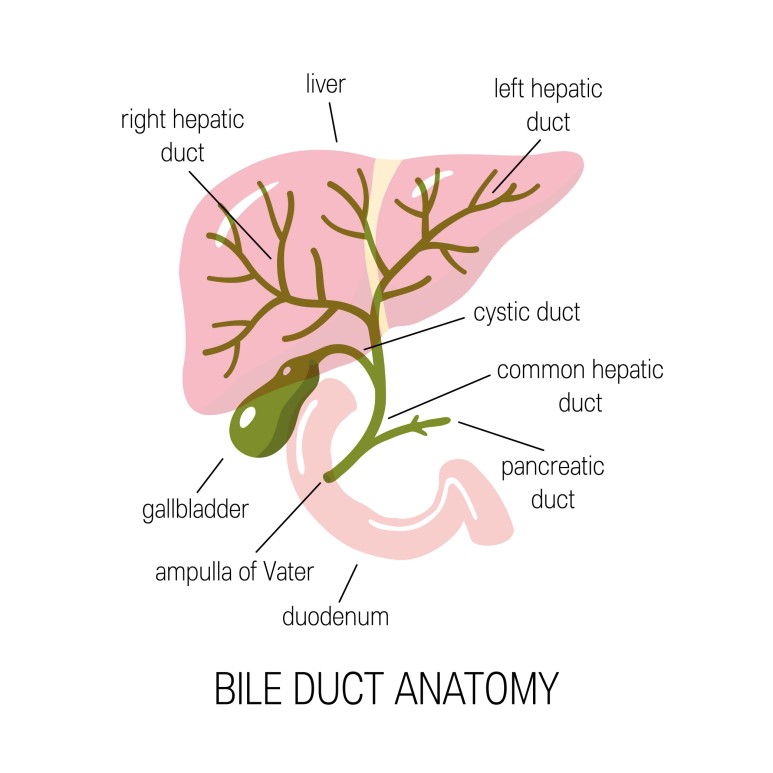

적혈구가 파괴되어 생기는 용혈성 황달도 있는데, 오늘은 담관 폐쇄로 인해 발생하는 용혈성 황달에 대해서 말씀드리겠습니다.

그 중 오늘은 폐쇄성 황달에 대해서 이야기를 해보도록 하겠습니다.

배쇄성 황달이 발생하는 원인은 다양한 총담관석, 담관협착, 담관 내 기생충,

Mirizzi 증후군, 원발성 경화 담관염, 췌장염, 혈액 담즙증 등을 들 수 있습니다.

또한 악성 질병에 해당하는 버터 팽대부 종양, 췌장암, 담관암, 십이지장암, 림프절과 간 전이로 담관을 압박하는 경우도 원인이 됩니다.

폐쇄성 황달이 나오는 원인은 담관이 막혀서 시작됩니다.

담관이 막혀 담관의 확장이 이루어지는데 처음에는 정상으로 보이는 경우가 있으나 시간이 지나면 문제가 발생합니다.

담관 담석과 양성 협착의 경우 보다 종양으로 인하여 담관이 막힐 경우 담관 확장이 더욱 심해집니다.

이렇게 담관이 확장된 경우에는 배액을 시행하면 담관의 크기가 이전과 같이 정상으로 돌아갑니다.

그러나 담관을 배액하고도 담관 확장이 계속 남아 있는 경우가 있는데 이는 담관 배액시기를 놓쳐 지연되면 발생합니다.

또한 담낭 관원위부의 총 담관이 막히는 경우 담즙의 압력 상승으로 담낭까지 확장될 수 있습니다.